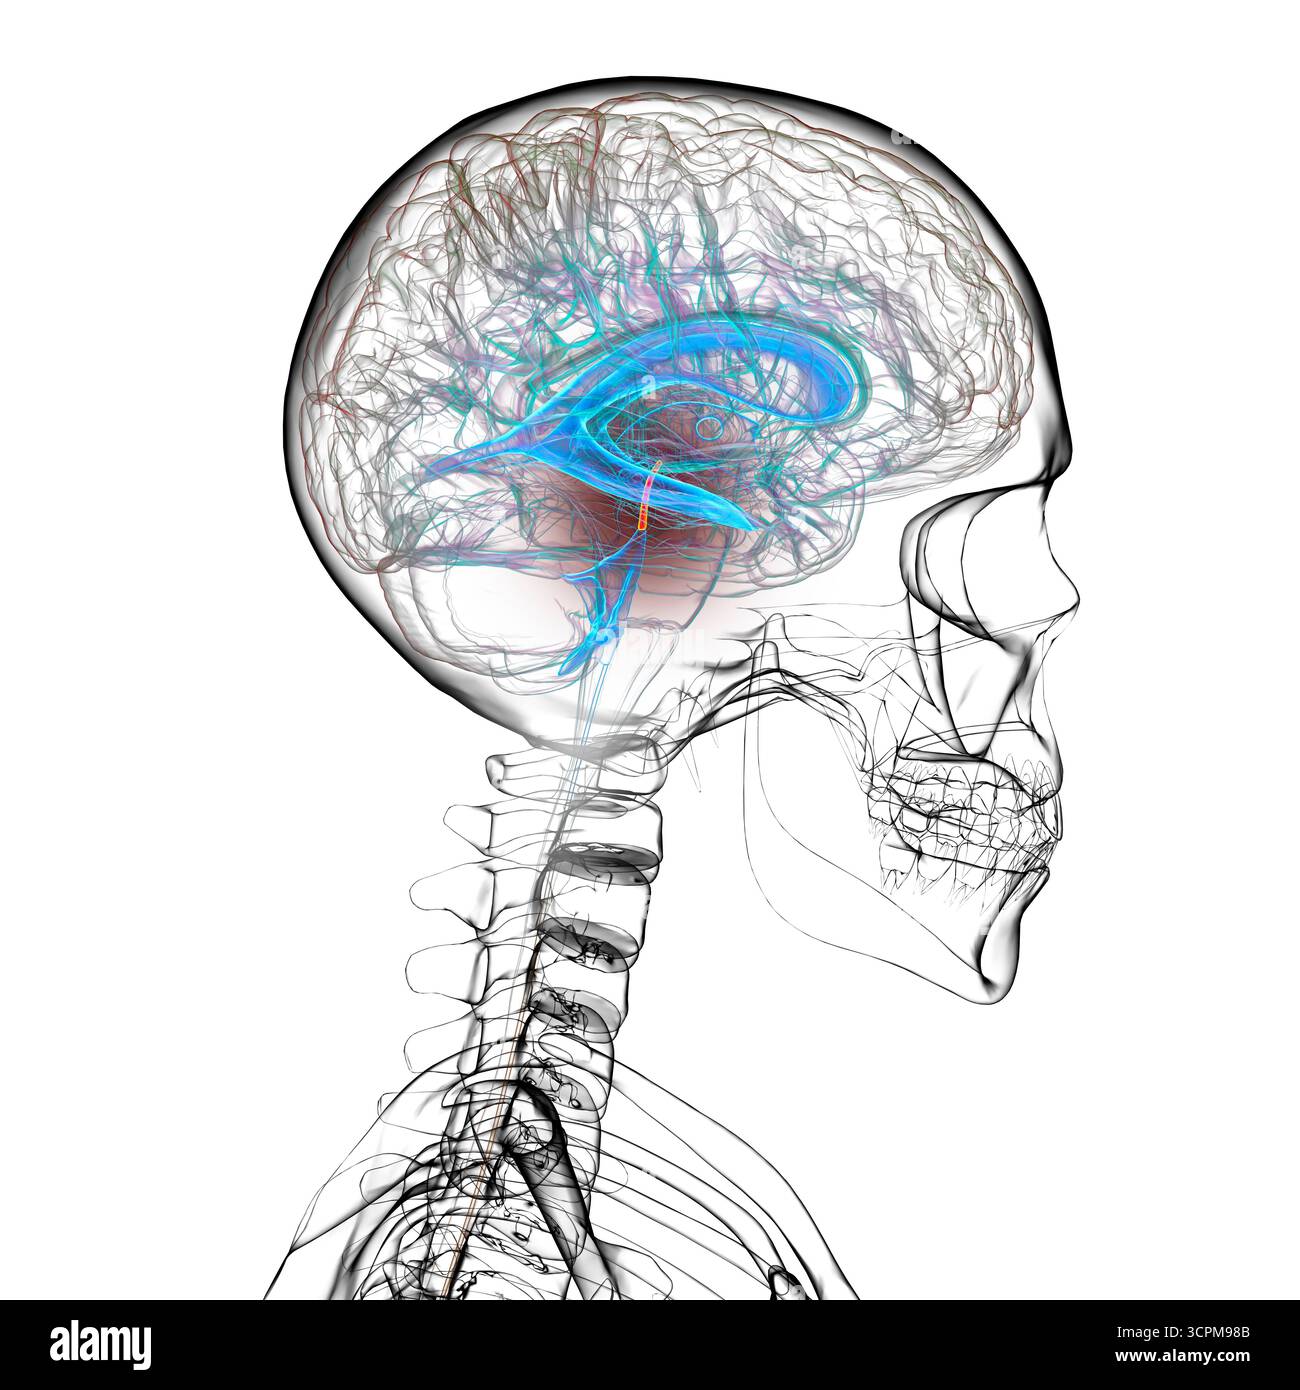

RF3CPM9C1–Illustration des dritten Hirnventrikels, einer lebenswichtigen Komponente des Hirnventrikulärsystems.

RF3CPM9BH–Illustration des dritten Hirnventrikels, einer lebenswichtigen Komponente des Hirnventrikulärsystems.

RF3CPM9BE–Illustration des dritten Hirnventrikels, einer lebenswichtigen Komponente des Hirnventrikulärsystems.

RF3CPM9BX–Illustration des dritten Hirnventrikels, einer lebenswichtigen Komponente des Hirnventrikulärsystems.